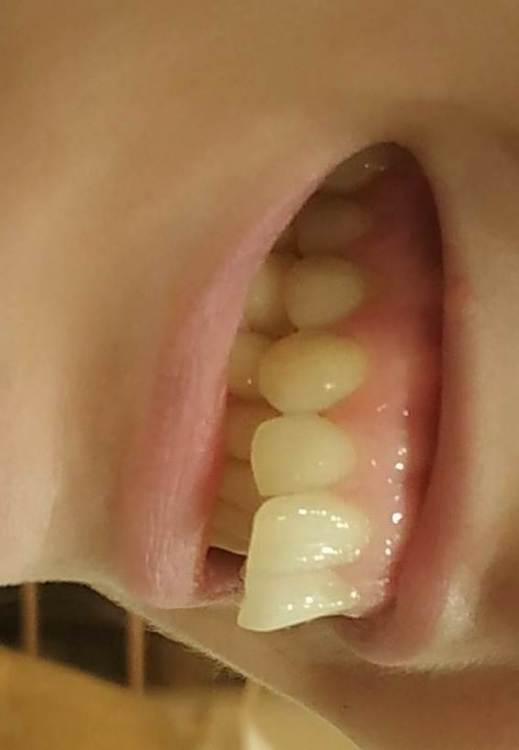

В феврале этого года заметила, что нить между клыком (23) и 24 зубом начала застревать. Зубы начали поднывать.

6 марта на осмотре стоматолог сказала, что  у меня кариес в 23 зубе (на границе с 24)

16 марта от 23 зуба откололся маааленький кусочек эмали (как раз на границе с 24 зубом), и зубы начали ныть днем и ночью

Болит вся область: 25, 24, 23 и 21. Особенно меня беспокоит 21. Он вообще здоровый, нелеченый зуб. А заныл просто дико!